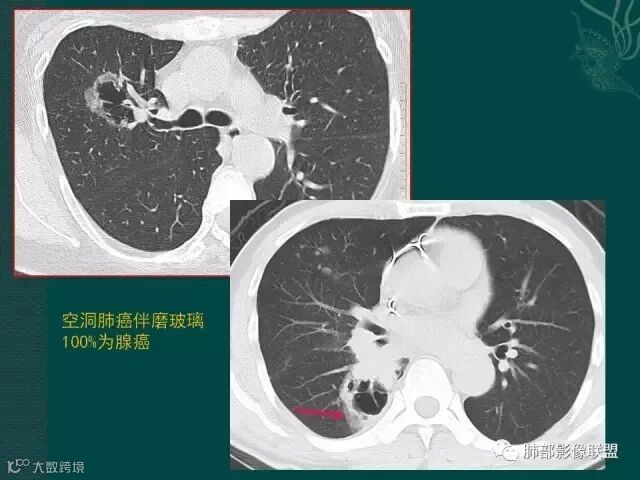

上一个是磨玻璃密度肺癌,边缘清晰,内有分隔,空洞型肺癌伴磨玻璃密度影的,100%为腺癌,很显然这是个假性空洞;

下一个也是肺癌,内有分隔,外下缘箭头所示也是磨玻璃影,这也是腺癌,同时可见叶间裂有转移灶。